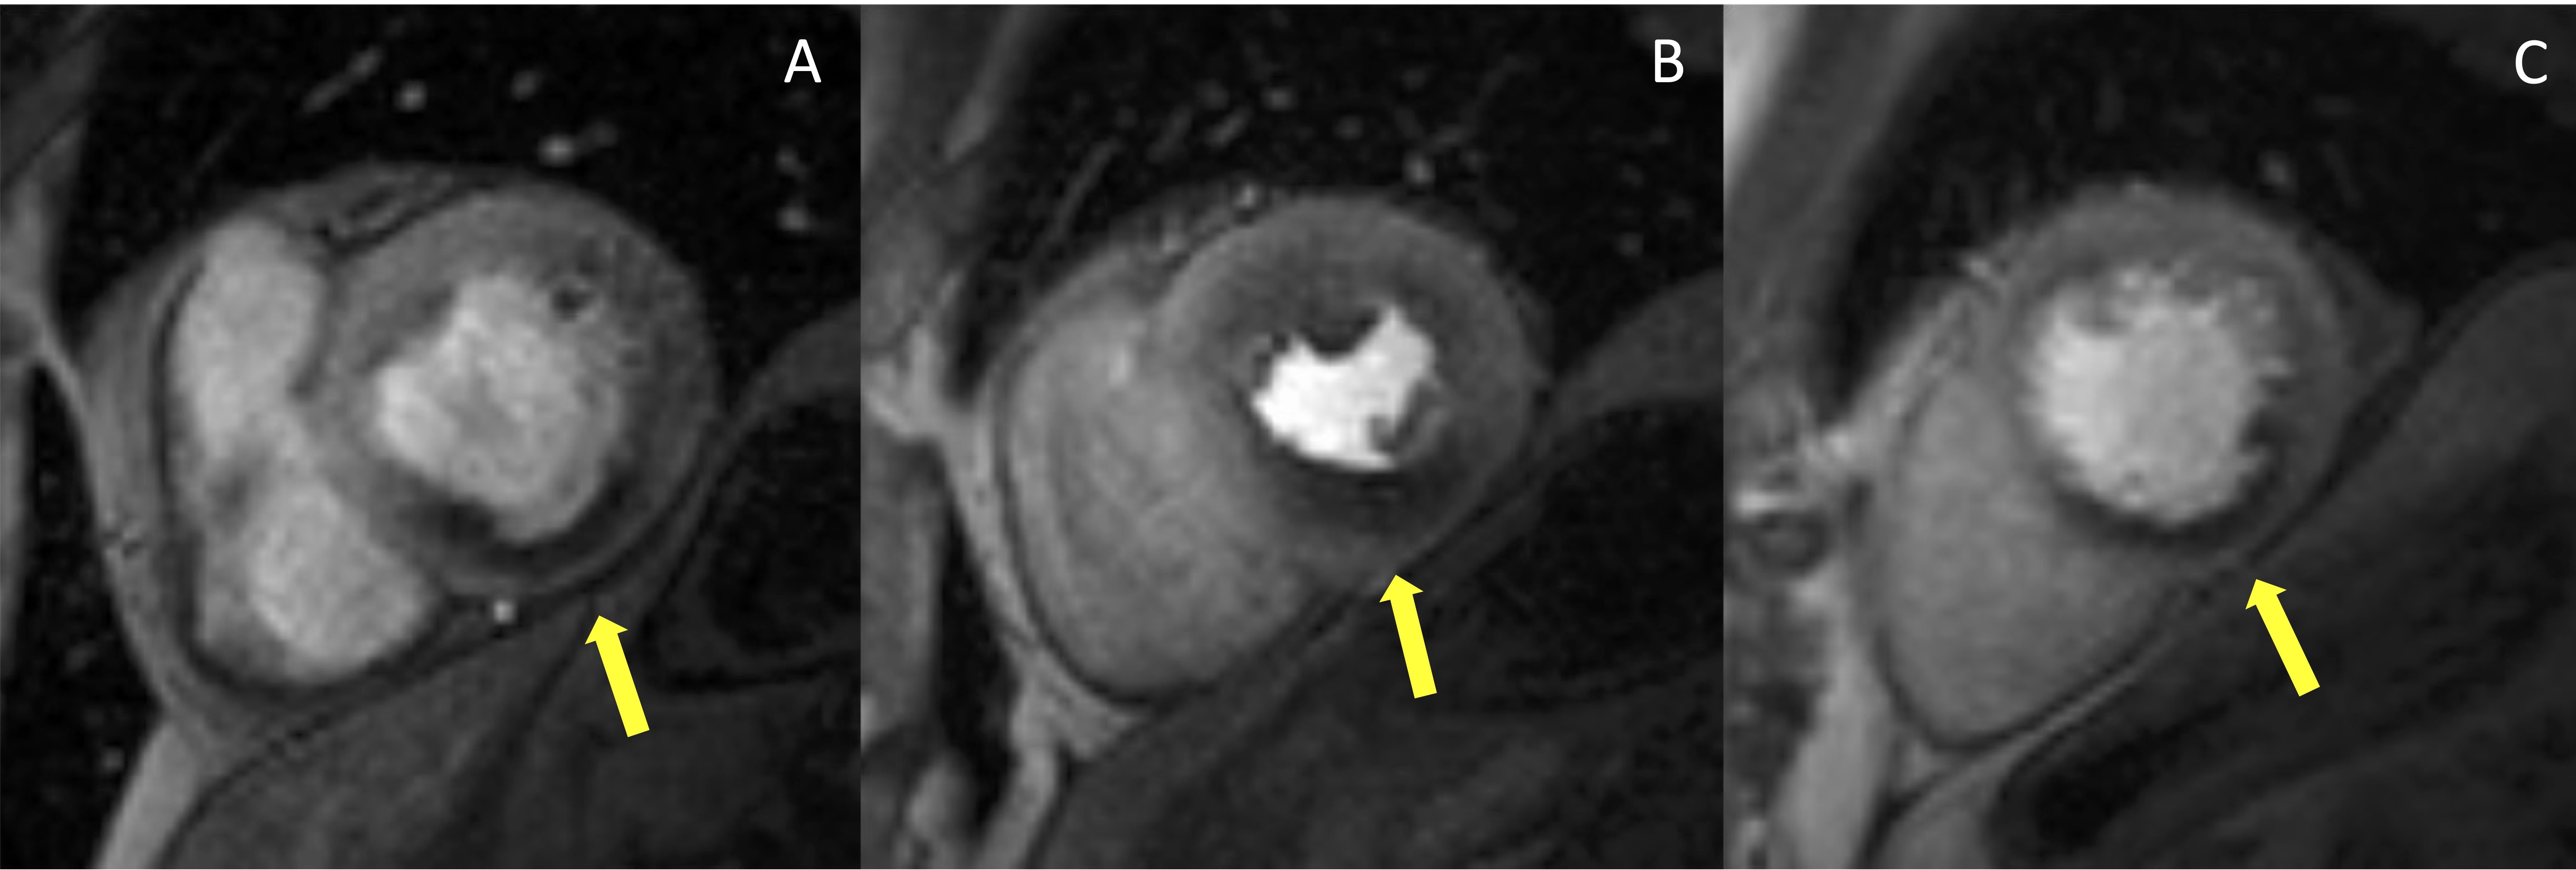

Stress CMR with vasodilators induces a myocardial perfusion defect with the coronary steal phenomenon. During the administration of a vasodilator, the blood flow is increased in regions perfused by normal coronary arteries and reduced in areas supplied by stenotic arteries. Once hyperemia is obtained, serial dynamic stress perfusion images are continuously acquired during administration of intravenous contrast agent. Images are usually acquired in a stack of three short-axis planes covering the entire ventricle and an optional long axis plane. Care should be taken to avoid the inclusion of the LV outflow tract in the most basal short-axis slice. The post-contrast signal enhancement is visualized as the injected gadolinium-based contrast agent enters into cardiac chambers and perfuses the myocardium. In normally perfused myocardial segments, the contrast agent will enter faster and evenly, inducing a quick and higher increase in T1 signal intensity compared to areas supplied by stenotic arteries [28]. Hypoperfused areas will show a segmental subendocardial hypointense stripe (Fig. 1). According to the 2019 ESC guidelines, high event risk in patients with established chronic coronary syndromes is defined by at least 2 of 16 segments with stress perfusion defects [27].

Fig. 1.Example of abnormal stress CMR. The first-pass perfusion images are usually acquired in three short axis slices, at the basal (A), mid (B) and apical (C) ventricular level during coronary maximal vasodilation. This example shows an inducible perfusion defect, appearing as a hypointense subendocardial area (indicated by the yellow arrow lines) in the inferior and infero-septal segments. CMR, cardiovascular magnetic resonance.